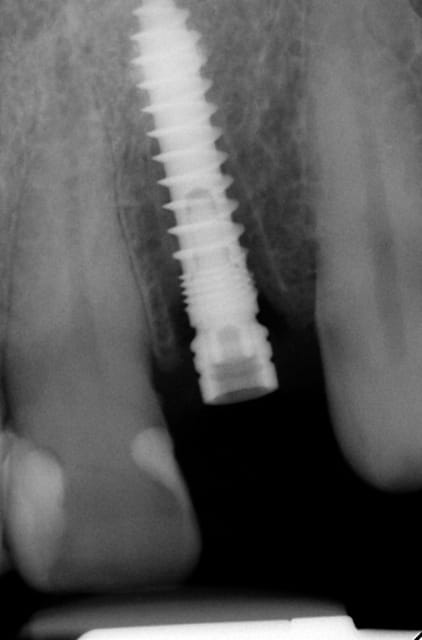

Merci pour tes questions. Si tu as une gencive "normale" (2-3 mm) ( avec le foret on peut savoir grâce aux mesures ) tu arrêtes à implanter si le truc en métal (je ne sais pas en francais en allemand Einbringhilfe) arrive à la gencive. Si la gencive fait plus de 3mm tu pousses un peu plus (le début de la fenêtre du Einbringhilfe est à un millimètre , la fin de la fenêtre = 3mm ) ...on vérifie avec une petite radio (pas OPG) .

Oui sans condenser juste en flapless ca serai moins évident. Pour moi-même en condensant j´ai besoin de 1 mm buccal minimum(plus il y a mieux c´est) mais dans ma pratique et celles mes confrères ca fonctionne et cela dure dans le temps depuis 16 ans.

En dessous il y a des photos, dans une on voit (troisième) qu il n y a pas de resorption de l´os après 14 ans, ce que l´on voit c´est l´os très fin condensé sur l´implant.